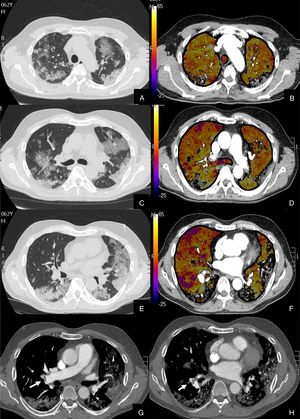

Paciente con COVID-19 que después de una semana de ingreso hospitalario persiste con desaturación que no corrige con flujo elevado de O2.

Imágenes axiales de la angiografía pulmonar con TC y mapa de yodo en ventana de parénquima (A, C, E, G) desde el cayado aórtico hasta los lóbulos inferiores y su correlación con el mapa de yodo (B, D, F, H).

Parénquima con afectación severa en vidrio deslustrado de predominio subpleural y segmentos posteriores de todo el pulmón, sin TEP visible. El mapa de yodo muestra una severa hipoperfusión difusa de todo el pulmón tanto afectado como sano (zonas azules y negras) en probable relación con microtrombosis difusa del lecho capilar.